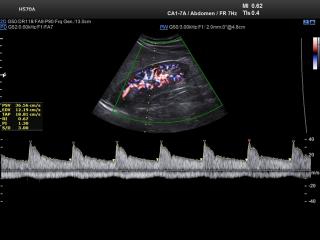

Kidney, CFM & PW

HS70. Kidney, CFM & PW.